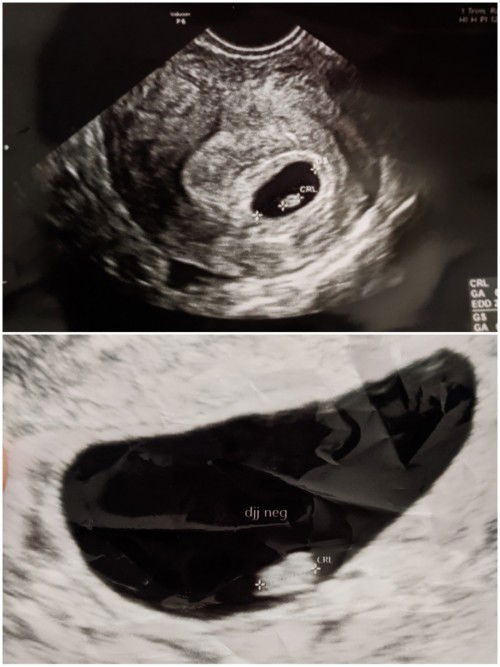

Selamat malam bunda. Aku ingin berbagi cerita. Aku mengalami keguguran lagi untuk yang kedua kalinya😢 Rasanya sedih banget bun. Keguguran pertama aku alami di bulan Maret 2022. Dan aku hamil lagi di bulan September, tapi keguguran lagi. Bener-bener sedih bgt bun🥺 Foto yang atas adalah hasil USG ku saat 6 minggu. Dokter bilang kantungnya bagus, dan udah ada calon janinnya juga. Dokter kemudian bilang kontrolnya 1 bulan lagi. Tapi belum genap sebulan, aku mengalami flek. Jadi aku langsung periksa ke dokter. Dan pas di USG (foto yang bawah), ternyata janinku nggak berkembang🥺 Hanya kantong rahimnya saja yang membesar. Harusnya usia kandunganku udah 10 minggu. Jadi dokter bilang, kandunganku udah nggak bisa dilanjut lagi dan dikuret. Rasanya hancur bgt dengernya. Aku sempat minta waktu 1 minggu lagi. Siapa tau ada keajaiban. Tapi belum ada 1 minggu, aku malah pendarahan banyak. Akhirnya aku cuma bisa pasrah😢😢😢 #sharing #sedih #firstmom